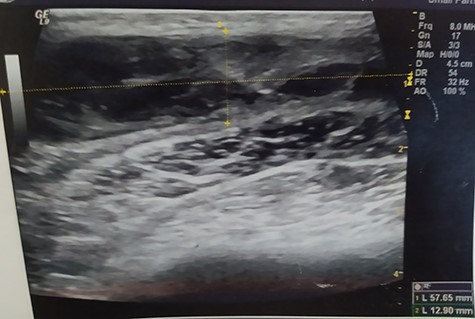

A 55-year-old Caucasian male proceeded to our institution complaining about irreducible swelling of the right iliac fossa and constant discomfort, over the course of a year. His medical history revealed that he slapped against a blunt surface of a furniture a year ago and injured his right groin and pelvis. Due to the accident and the subsequent painful swelling, the patient underwent immediately a pelvic ultrasound the detected an acute hematoma with a diameter of 52 mm into the fatty tissue of the right pelvic fossa (Fig. 1). Ten months after the accident, due to the irreducible swelling, the patient underwent another ultrasound revealing a nonorganized hematoma with thrombotic features (sized as 25 × 60 × 58 mm) (Fig. 2).

Pelvic ultrasound indicating an acute hematoma into the fatty tissue of the right iliac fossa.